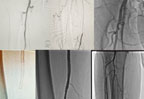

Skleroterapiyaların nəticələri